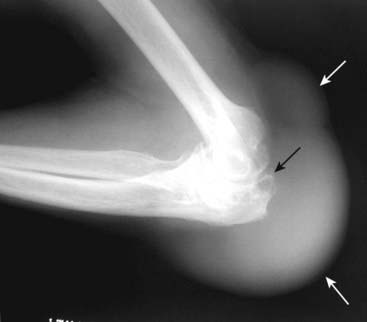

Figure 23-17 Olecranon bursitis in gout.

Olecranon bursitis is a common manifestation of gout (large soft tissue mass around elbow shown by solid white arrows) and its presence alone should alert you to the possibility of underlying gout. This patient also displays erosions adjacent to the elbow joint (solid black arrow).